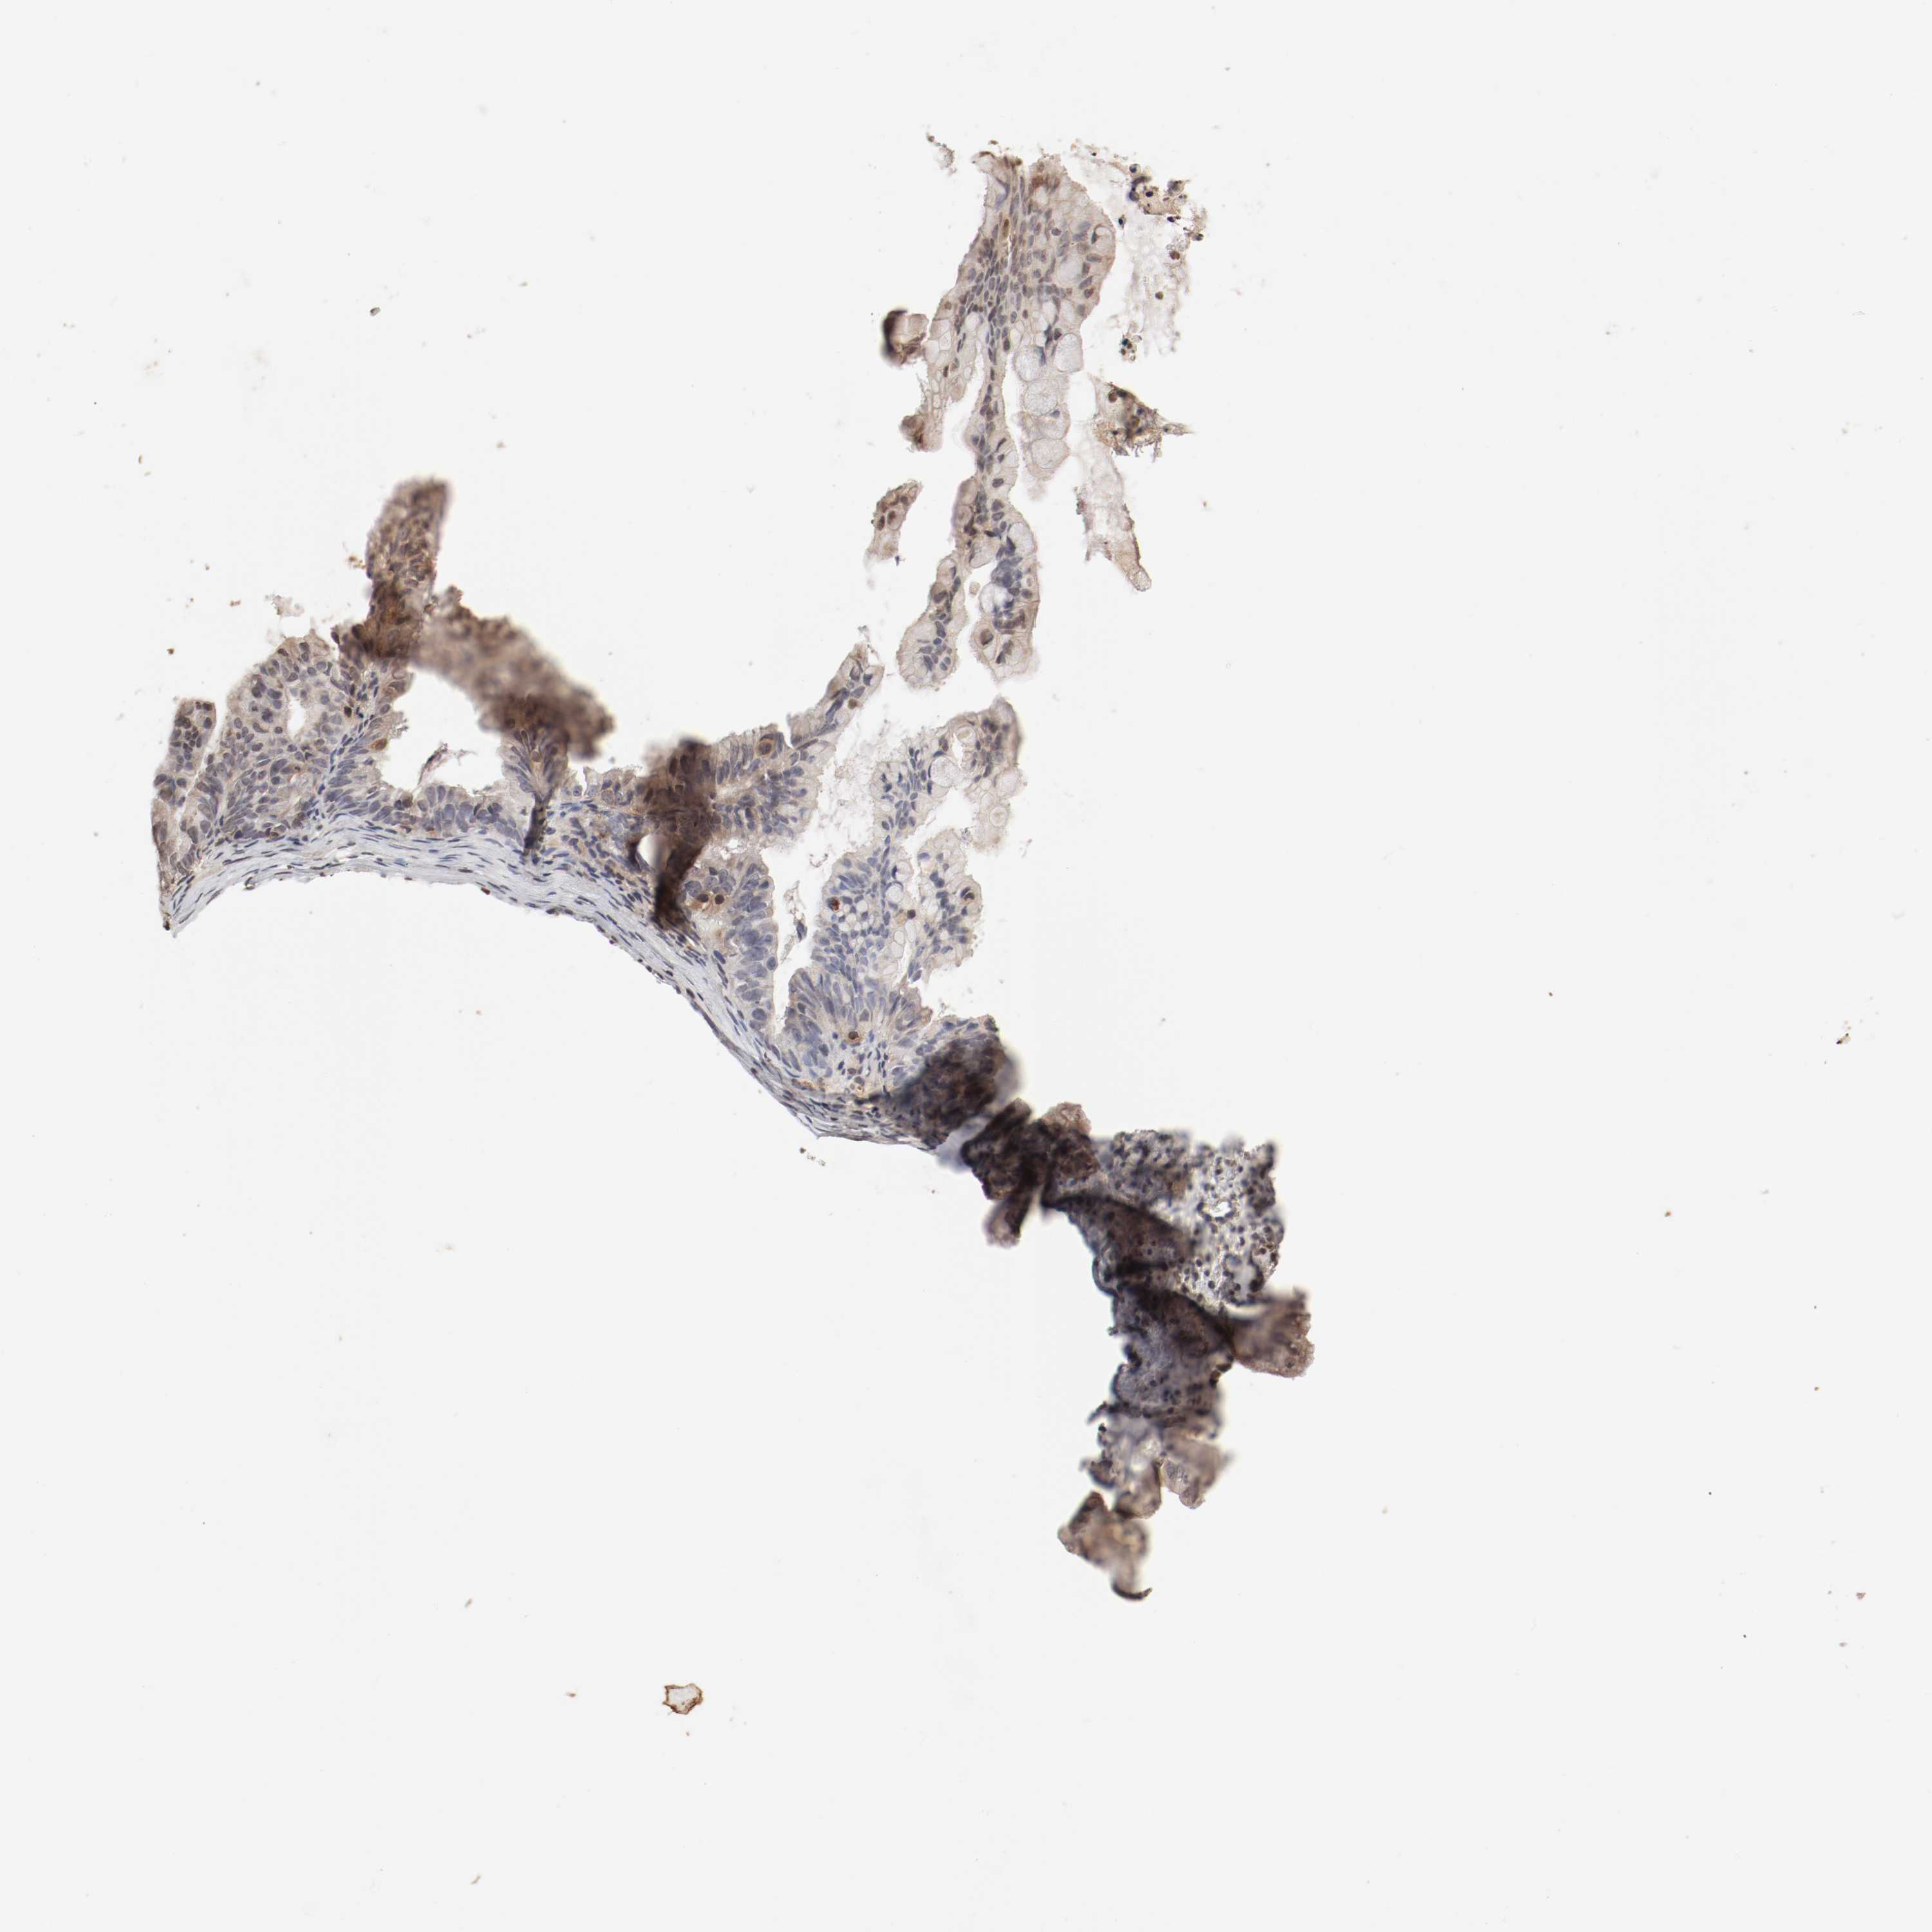

OVARIAN CANCER - Protein expressioni

A mouse-over function shows sample information and annotation data. Click on an image to view it in a full screen mode. Samples can be filtered based on level of antibody staining by selecting one or several of the following categories: high, medium, low and not detected. The assay and annotation is described here.

Note that samples used for immunohistochemistry by the Human Protein Atlas do not correspond to samples in the TCGA dataset.

Antibody stainingi

Antibody staining in the annotated cell types in the current human tissue is reported as not detected, low, medium, or high, based on conventional immunohistochemistry profiling in selected tissues. This score is based on the combination of the staining intensity and fraction of stained cells.

Each image is clickable and will lead to virtual microscopy that enables deeper exploration of all samples and also displays staining intensity scores, fraction scores and subcellular localization as well as patient and tissue information for each sample.

Antibody HPA005750

Antibody CAB005399

Cystadenocarcinoma, serous, NOS

Carcinoma, endometroid

Cystadenocarcinoma, mucinous, NOS

Carcinoma, NOS